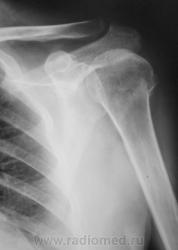

Есть перелом, или нет перелома?

Есть, возм. патологический.

Есть.

перелом шейки, не обязательно патологический.

есть метастаз рака почки, либо меланомы, это к патологическому перелому.

Честно говоря, явно "патологического" характера перелома не вижу. Коллеги, поделитесь, пожалуйста, аргументами - откуда такая уверенность в онкологии?

оскольчатый внутрисуставной перелом проксимального эпиметафиза левой плечевой кости, с фрагментацией большого бугорка, либо изолированный внутрисуставной перелом большого бугорка. так  же интересно было бы узнать аргументы за патологический перелом

Вколоченный перелом х/шейки плечевой кости. Возможно, не свежий.

Но мы не знаем и анамнеза. По крайней мере если не деструкция, то остеопороз есть. Возможно не свежая травма, что отметил lupan?

Травма 2 суток тому.